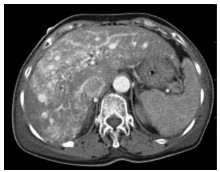

Expert consensus on the imaging diagnosis of hepatic echinococcosis

Radiology of Infection Sub-branch, Radiology Branch, Chinese Medical Association, Committee on Radiology of Infectious, Radiology Branch, Chinese Medical Doctor Association

2021, 37(4): 792-797. DOI: 10.3969/j.issn.1001-5256.2021.04.014

Abstract(1370) HTML (648) PDF (2065KB)(146)

Abstract:

Echinococcosis is a zoonotic disease with global distribution and has become an issue seriously affecting public health around the world. Imaging technology plays an important role in the early diagnosis, preoperative evaluation, and treatment outcome monitoring of hepatic echinococcosis. At present, no consensus has been reached on the imaging diagnosis of echinococcosis, which brings difficulties in the learning and training of imaging professionals and the standard diagnosis and treatment of echinococcosis in clinical practice. For this reason, Beijing YouAn Hospital, Capital Medical University, and The First Affiliated Hospital of Xinjiang Medical University organized the radiologists engaged in infection and inflammation from several hospitals to reach a consensus on the basis, principles, and criteria for the imaging diagnosis of echinococcosis and the differential diagnosis of echinococcosis, with reference to international guidelines, related articles, the latest research findings in China and globally, and the methodological requirements for the establishment of guidelines and standards in evidence-based medicine, so as to provide a clear diagnostic basis for clinicians in the clinical application of hepatic echinococcosis imaging.